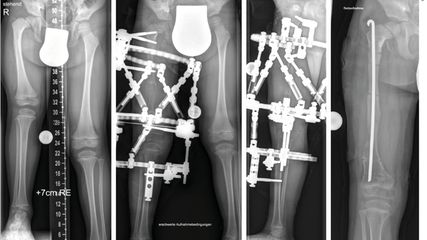

Angeborene Fehlstellungen des Unterschenkels

Kongenitale Deformitäten des Unterschenkels gehören zu den seltenen, aber medizinisch bedeutenden und operativ herausfordernden Diagnosen der Kinderorthopädie. Eine differenzierte ...